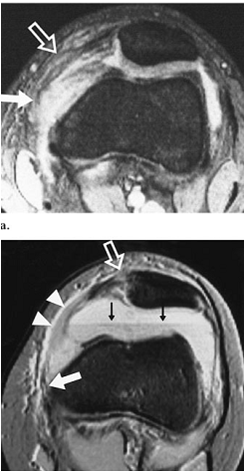

This is an example of a scan showing ruptured medial patellofemoral ligament after an acute lateral patellar dislocation:

What Happens to the Medial Patellofemoral Ligament After an Acute Lateral Patellar Dislocation?

•Torn in 94-100% of patients with LPD at open surgery

•Usually at or close to its femoral origin

•Multiple sites of injury to medial ligamentous restraints in 48%